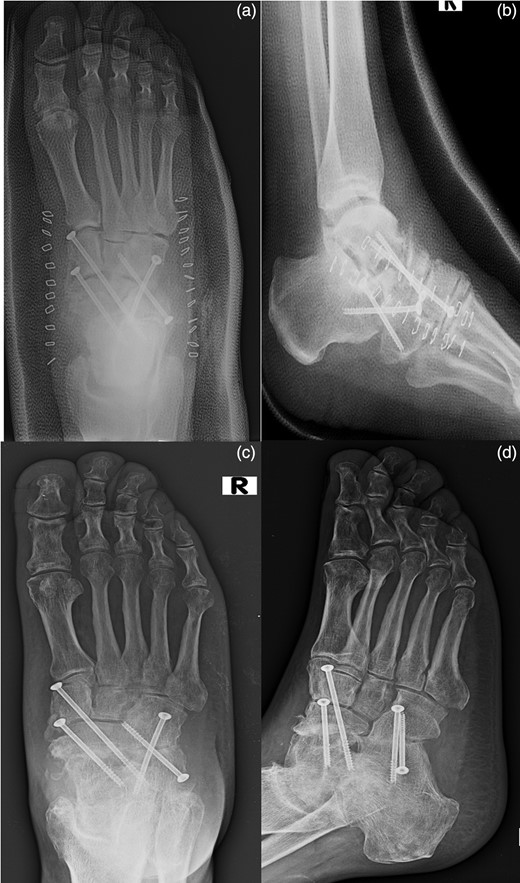

At the sixth month follow-up, the patient had returned to work and remained pain free while walking, with good fusion of both joints (Fig. 5).

AP (a) and lateral (b) radiographs of the foot in the cast after the surgical time. AP (c) and lateral (d) radiographs of the foot at the sixth month follow-up.